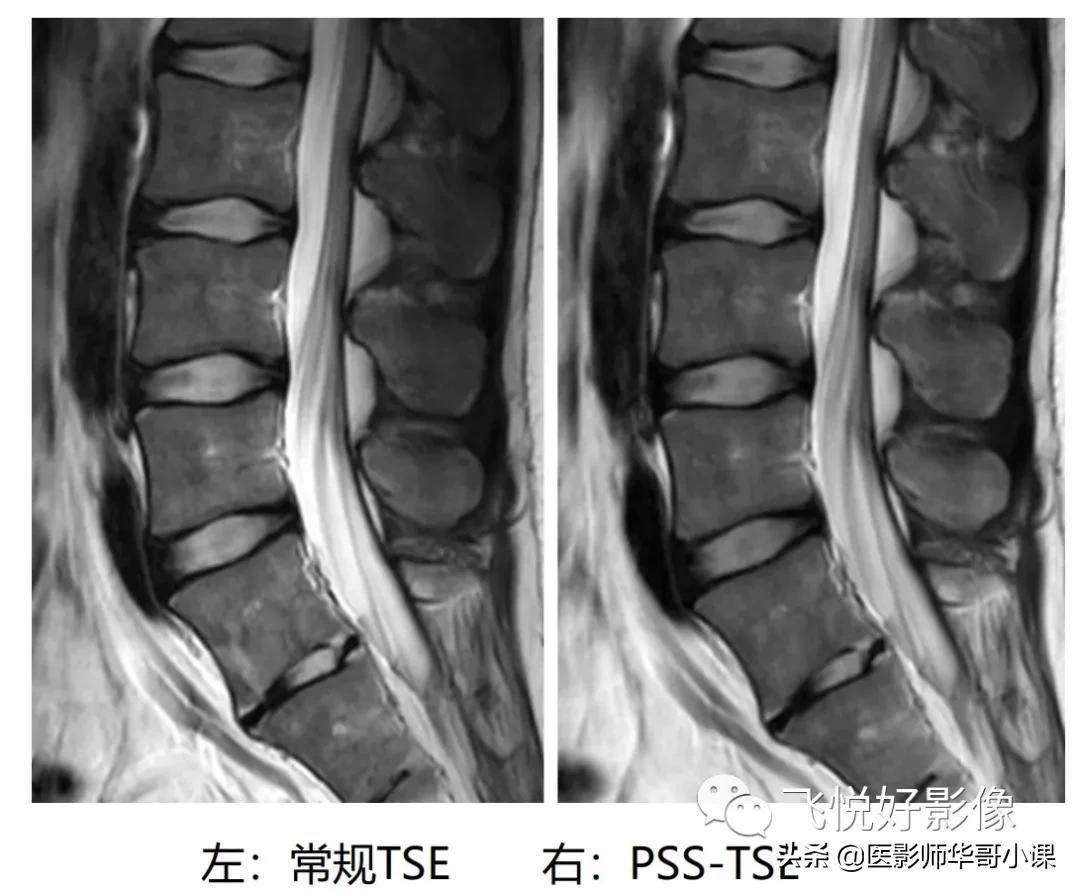

图9.常规TSE与PSS-TSE

上述两图对比可以看出,使用PSS-TSE的图像中椎体边缘及终丝锐利度提高,运动伪影也有所减少。